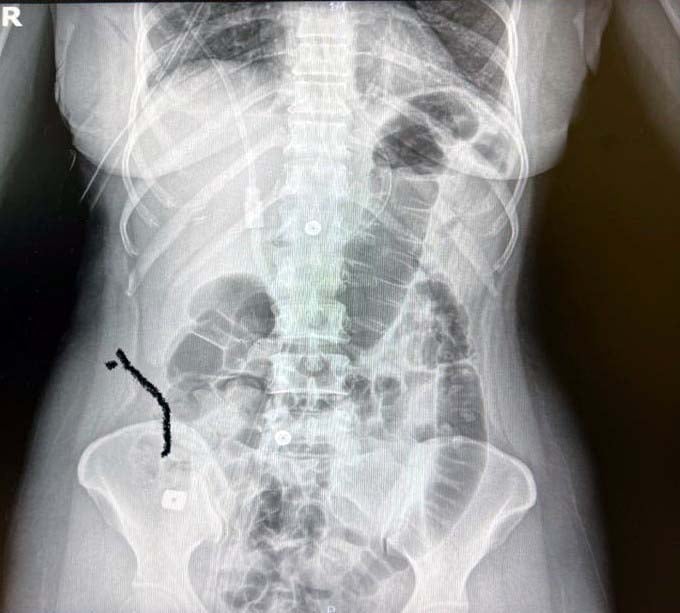

Prof Dr. Levent Elbeyli, bilinci kapalı olarak hastaneye getirilen Sultan Tıraş’ın, hayatını kaybetme riski çok yüksek bir olay yaşadığını vurguladı. Yaşanan bu olayın tıp literatüründe görülmediğini belirten Elbeyli, yapılan radyolojik tetkikler ve değerlendirmeler sonucu daha önce başka bir merkezde boyun omurlarına yerleştirilen metal disklerin yerinden oynadığını ve birisinin de midede olduğunun tespit edildiğini kaydetti.

Yaptığımız incelemelerde bu implantların yerinden oynadığı ve bir şekilde yer değiştirdiğini gördük. Bu alan komplike bir alan. Yapılan endoskopide yemek borusunda bir delinme olduğunu tespit ettik. Devamında midede bu implantların birinin görünmesi söz konusu. Diğer implantın da yerinden oynadığını görüyoruz. Böyle bir durumda hayati tehlikesi son derece yüksek.